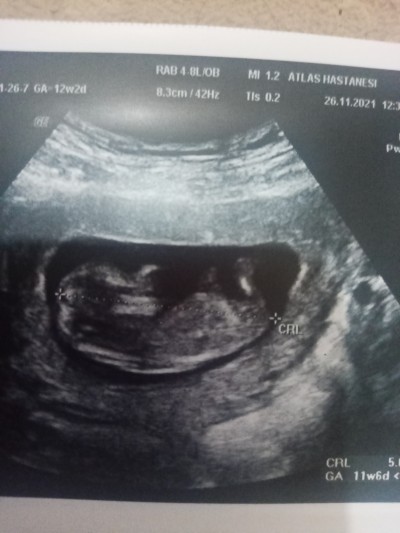

Kızlar sizce cinsiyeti nedir bu gün doktora gittim doktor hiç birşey söylemedi

Gebelik haftası 12+2